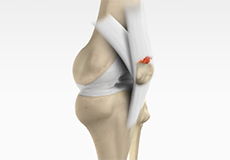

Posterolateral Instability

Posterolateral instability, also known as posterolateral rotatory instability (PLRI), is a common pattern of knee instability that results from injuries to the structures that support the outside of the knee joint, the posterolateral corner. When individuals injure the knee ligaments, they are most likely to injure the structures of the posterolateral corner.